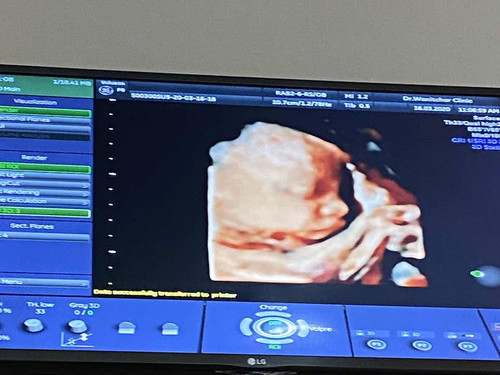

ไปอุตาร์ซาวมา30w4dหมอบอกน้องน้ำหนัก 1.8 เกินกว่ามาตรฐาน ?